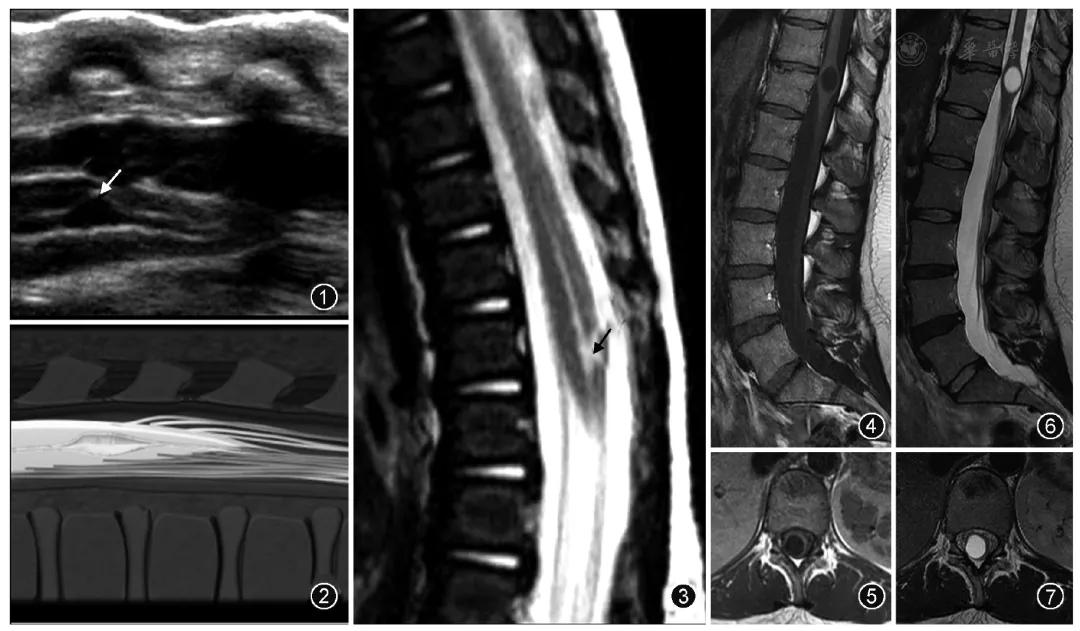

第五脑室,也称终室(ventriculus terminalis, VT),是位于脊髓圆锥内、由正常室管膜组织包绕且内含脑脊液的囊性腔室。该腔室结构由Stilling在1859年首次描述为与蛛网膜下腔相通且扩张的脊髓中央管,但Krause不认同Stilling提出的该腔室与蛛网膜下腔相通的观点,并于1875年在观察到这个囊腔的壁是由正常室管膜细胞构成后提出了"第五脑室"这一概念。

在儿童时期,无临床症状的第五脑室被认为是一种正常的发育现象,无需进行干预,但是也有部分具有第五脑室的儿童,合并一些先天畸形,例如脊髓栓系综合征、脊髓脊膜膨出、腰骶部脂肪瘤等。成人的第五脑室可以没有任何临床症状,但当脊髓圆锥受到第五脑室压迫时,可产生括约肌功能障碍,运动和感觉功能异常,坐骨神经痛等症状。

超声是诊断胎儿或新生儿第五脑室的一种常用检查方法。第五脑室在超声矢状切面图上显示为脊髓圆锥区域囊状扩张的低回声区并可与中央管相通,在超声横断切面图上表现为扩张的低回声囊腔且与周围脊髓组织有着较为清楚的分界。

来自杂志图片

MR检查为诊断第五脑室的主要手段。第五脑室在MRI上通常表现为脊髓圆锥内边缘清楚的卵圆形囊腔,形态规则,囊壁光整,且与周围正常的脊髓组织分界清楚,囊内为T1WI低、T2WI高的脑脊液信号,囊内分隔及囊周水肿性改变比较少见,增强扫描后囊壁不强化。第五脑室需要与位于脊髓圆锥的囊性肿瘤如室管膜瘤、星形细胞瘤以及脓肿相鉴别,囊性肿瘤和脓肿的囊壁通常有不同程度的强化。脊髓圆锥的转移瘤很少见,MRI表现通常为肿瘤强化且周围伴有明显水肿。脊髓背侧的严重损伤也可发展为囊性病灶,但目前报道的大多数第五脑室病例并无外伤病史。脊髓内的表皮样囊肿和皮样囊肿由于成分复杂导致MRI表现多变,而第五脑室的MRI表现单一。